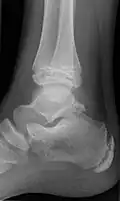

Ankle

Accessory bones at the ankle mainly include:

- Os subtibiale, with a prevalence of approximately 1%.[14] It is a secondary ossification center of the distal tibia that appears during the first year of life, and which in most people fuses with the shaft at approximately 15 years in females and approximately 17 years in males.[14]

- Os subfibulare, with a prevalence of approximately 0.2%.[15]

Os trigonum (further described below) may also be seen on an ankle X-ray.

The os trigonum or accessory talus represents a failure of fusion of the lateral tubercle of the posterior process of the talus bone. Is estimated to be present in 7–25% of adults.[17] It can be mistaken for an avulsion fracture of lateral tubercle of talus (Shepherd fracture) or a fracture of the Stieda process. In most cases, Os Trigonum will go unnoticed, but with some ankle injuries it can get trapped between the heel and ankle bones which irritates the surrounding structures, leading to Os Trigonum Syndrome.[21]